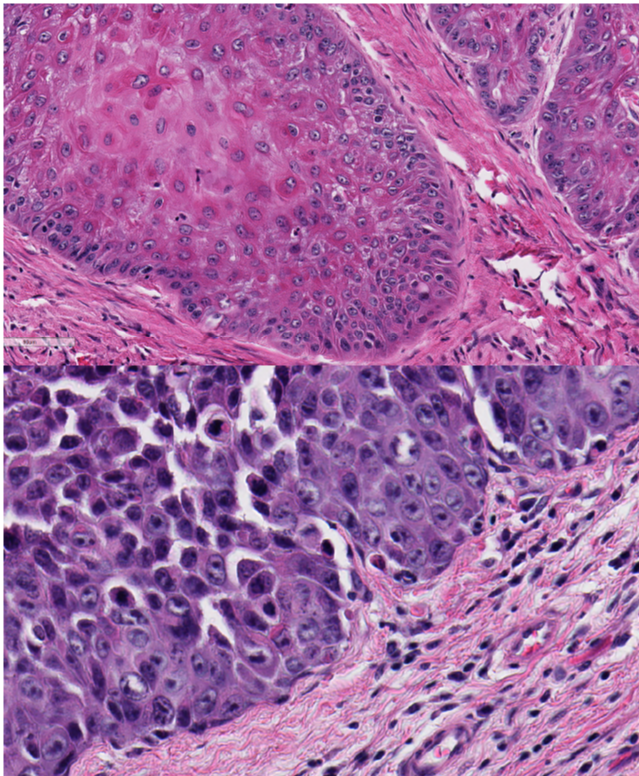

Identify this structure:

A

keratin pearl

4

Q

This is from the eyelid and ocular bone, provide a histologic morphologic diagnosis. (Note: there is metastasis to the lung)

ocular squamous cell carcinoma with local bone invasion and pulmonary metastasis

Which tissue layers are affected by the neoplasm?

Is the cell of origin a round cell, epithelial, or mesenchymal population?

epithelial - formation of cords, nests by cohesive groups of polygonal cells

This is from a feline larynx, is this benign or malignant and why?

malignant, the presence of neoplastic clusters within the blood vessels, severe stromal invasion, lack of differentiation, increased mitotic rate, cellular variability